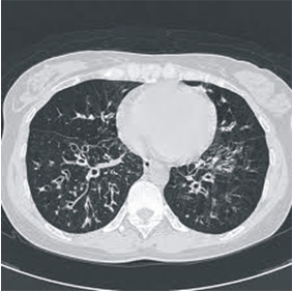

最基本的是進行胸部X光檢查,有經驗的胸腔科醫師能透過一張X光得到相當多的訊息,當X光有異常時,須安排進一步的痰液或抽血檢查。當以上檢查都無法確定診斷時,可藉助支氣管鏡檢查尋找出血位置。而高解析度胸部電腦斷層檢查可以全面掃描肺部異常變化,對支氣管擴張症的診斷更具價值。對於不明來源的大量咳血,支氣管血管攝影術可用於定位出血點並可同時作栓塞治療以止血。

高解析度胸部電腦斷層下的支氣管擴張症